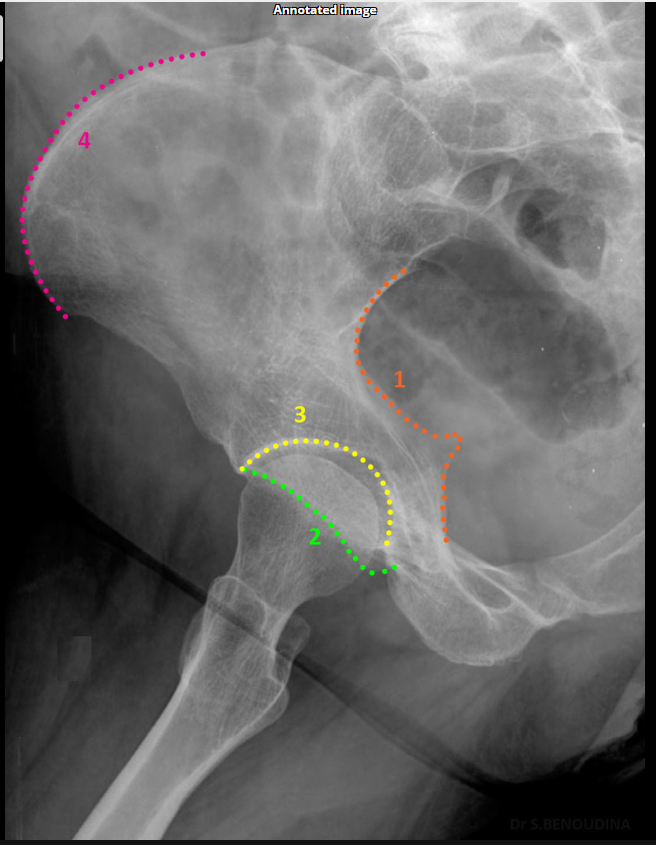

Which acetabular rim does the external oblique Judet view show?

Anterior rim. (SHOWN #2 GREEN)

<p>Anterior rim. (SHOWN #2 GREEN)</p>

Which acetabular column does the external oblique Judet view show?

Posterior column.ilioschial(SHOWN #1 ORANGE)

<p>Posterior column.ilioschial(SHOWN #1 ORANGE)</p>

What does the iliopubic line represent in Judet views?

Anterior column.(SHOWN #1 RED)

<p>Anterior column.(SHOWN #1 RED)</p>

What does the ilioischial line represent in Judet views?

Posterior column.(SHOWN #1, ORANGE)

<p>Posterior column.(SHOWN #1, ORANGE)</p>